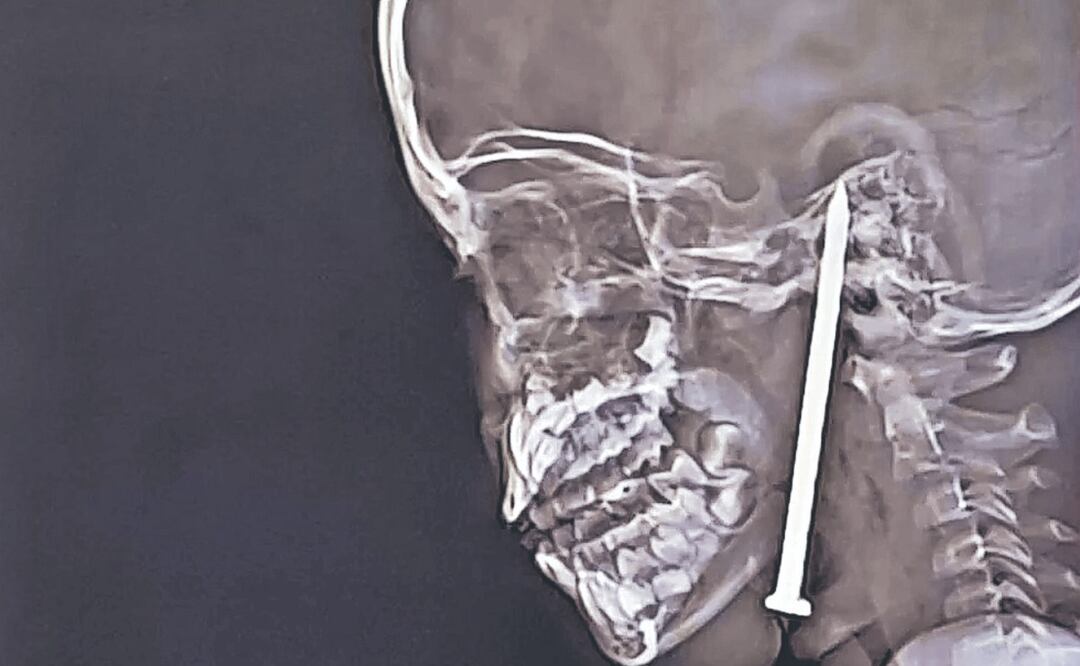

Tras evaluarla, el equipo médico le realizó resonancias magnéticas y tomografías computarizadas, las cuales revelaron que la punta del clavo le había penetrado el cuello y la mandíbula antes de llegar al cerebro.

La pieza de hierro incrustada en el cerebro de la niña medía 8 cm. En ese sentido, Sandip Tiwari, doctor a cargo de la operación, señaló que “el clavo no había tocado un vaso sanguíneo importante por un margen muy pequeño, lo cual fue sorprendente”.